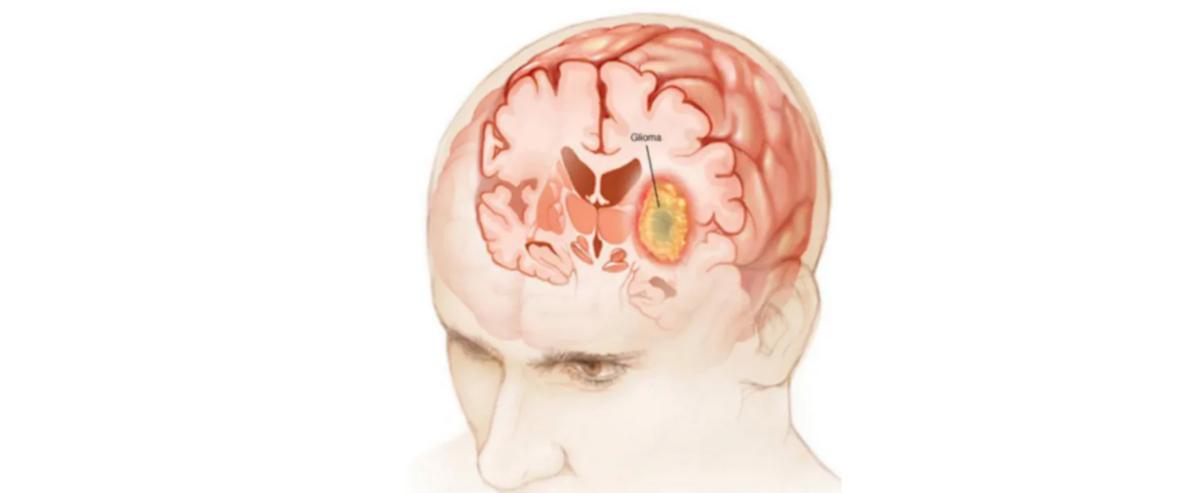

• 大叔最易中招脑瘤

脑子里长瘤是件恐怖的事儿,老百姓俗称的“脑癌”就是脑胶质瘤,偏偏“钟爱”四五十岁的中年大叔。脑胶质瘤在原发性脑瘤中发病率居首位,成为除胰腺癌之外死亡率最高的癌症,也最易侵袭中年男性。  脑胶质瘤是最为...【全文】